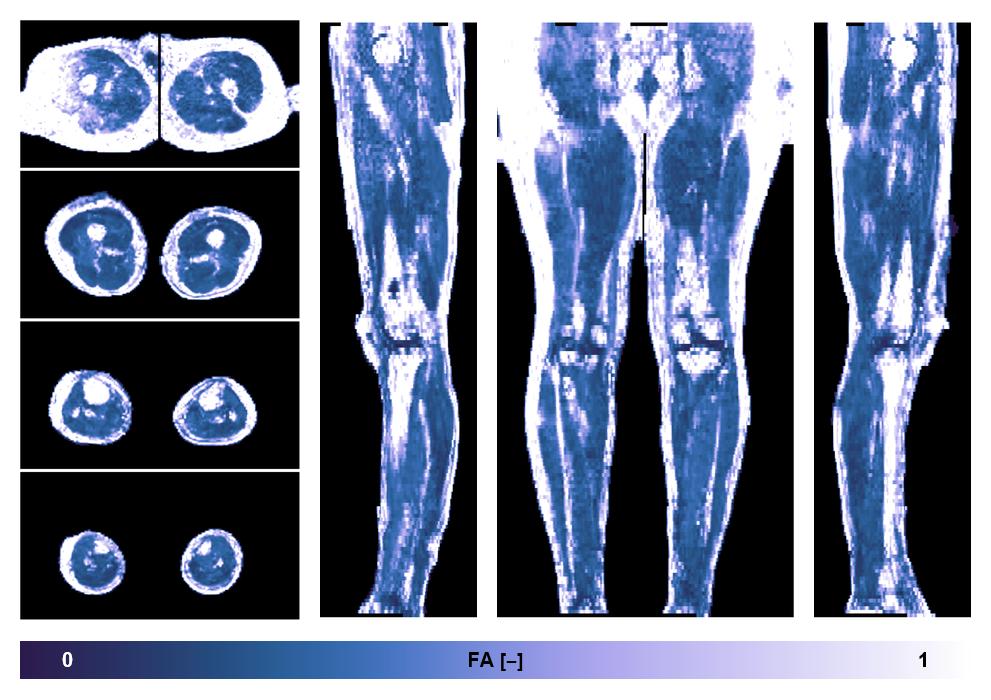

Diffusion tensor imaging

Diffusion weighted imaging with IVIM and DTI fitting to obtain muscle microstructure and muscle architecture, for information look here».

• Fractional anisotropy

IVIM corrected whole leg muscle fractional anisotropy obtained from diffusion tensor imaging.